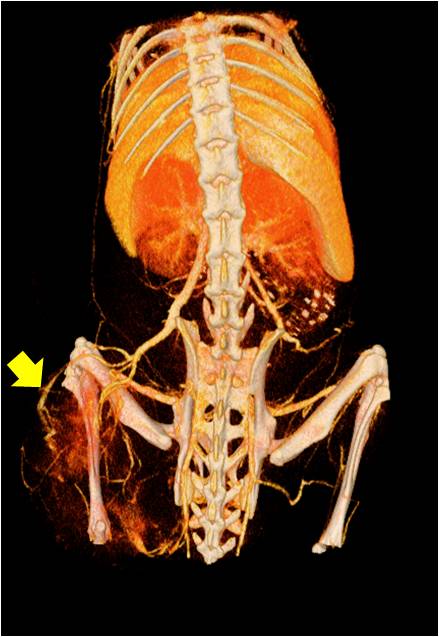

腫瘤血管生成

肺轉移

小鼠模式,22.5μm像素